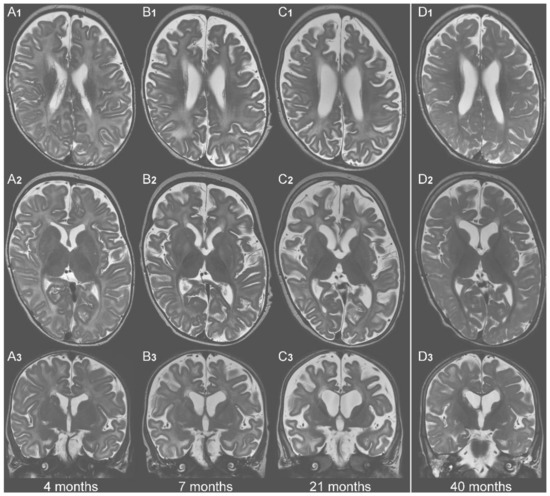

| No KD | KD | No KD | KD | |||||

| Age | 4 m | 7 m | 21 m | 40 m | 4 m | 7 m | 21 m | 40 m |

| white matter concentrations | basal ganglia concentrations | |||||||

| Lac (mM) | 0.73 | 2.01 | 2.53 | 0.98 | 0.73 | 0 | 2.57 | 1.54 |

| mI (mM) | 6.42 | 6.14 | 10.1 | 4.66 | 4.7 | 10.67 | 6.81 | 4.84 |

| Asp (mM) * | 0 | 0 | 0 | 0.68 | 0 | 0.16 | 0.21 | 1.11 |

| NAA (mM) | 3.67 | 2.35 | 2.07 | 3.08 | 3.63 | 3.47 | 3.19 | 3.42 |

| white matter NAA/Cr-ratio | basal ganglia NAA/Cr-ratio | |||||||

| NAA/Cr | 0.45 | 0.46 | 0.32 | 0.38 | 0.7 | 0.34 | 0.37 | 0.4 |

| Glyc (aU) * | 5.73 | 33.44 | 20.92 | 6.4 | 13.04 | 20.64 | 23.88 | 0 |

| Abbreviations: Lac = lactate, mI = myo-inositol, Asp = aspartate, NAA= N-acetyl-aspartate, Cr = creatinine, Glyc = glycerol, aU = arbitrary unit (scaling factor based on a phantom of known glycerol-3-phosphate concentration), m = month(s) * = no reference values available. Means and SD of mI/NAA-concentrations are age-dependent and were taken from Pouwels et al. [37] (cf. their tables 3 & 6) | ||||||||

| Color codes: | normal (for Lac <2mM; for mI: within mean ± 2.5 SD [37]) | |||||||

| increased (for Lac >2mM; for mI: above mean + 2.5 SD [37]) | ||||||||

| reduced (for NAA: below mean−2.5 SD [37]; NAA/Cr: <1) | ||||||||